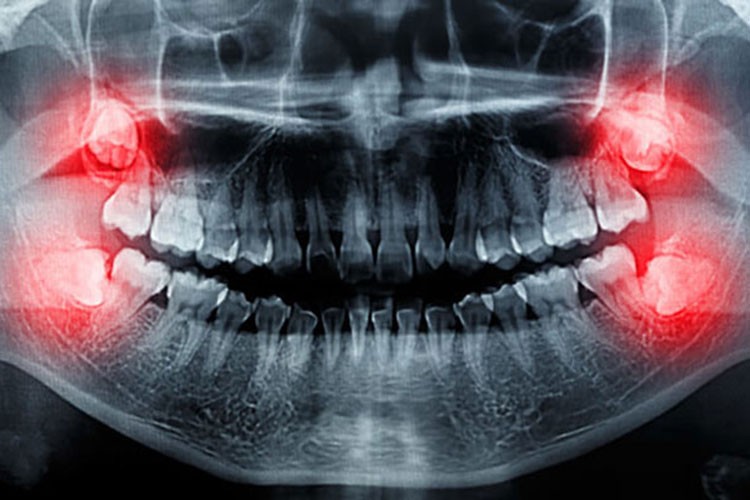

Yirmilik dişlerin çene yapısına sığmadığı durumlarda diğer dişlere baskı yaparak onların pozisyonunu bozabileceğini belirten Dr. Ümit Sait Yavuz, "Yirmilik dişler zamanında çekilmezse dışarı çıkabilmek için yaptığı baskıyla diğer dişlerin formunu bozabilir. Bu durum, özellikle diş teli tedavisi görmüş hastalar için daha da riskli. Çünkü diş teli tedavisiyle düzeltilen dişlerin yeniden bozulmasına neden olabilir. Güzel bir gülümseme, inci gibi dişler için yıllarca verilen emek boşa gidebilir" dedi.

Yirmilik dişlerin sadece diş sağlığını değil, gülüş estetiğini de olumsuz etkileyebileceğini ifade eden Yavuz, "Yirmilik dişlerin neden olduğu baskı, diğer dişlerin yamuk veya çarpık olmasına yol açabilir. Bu durum gülüş estetiğini bozar ve kişinin özgüvenini olumsuz etkiler" şeklinde konuştu.